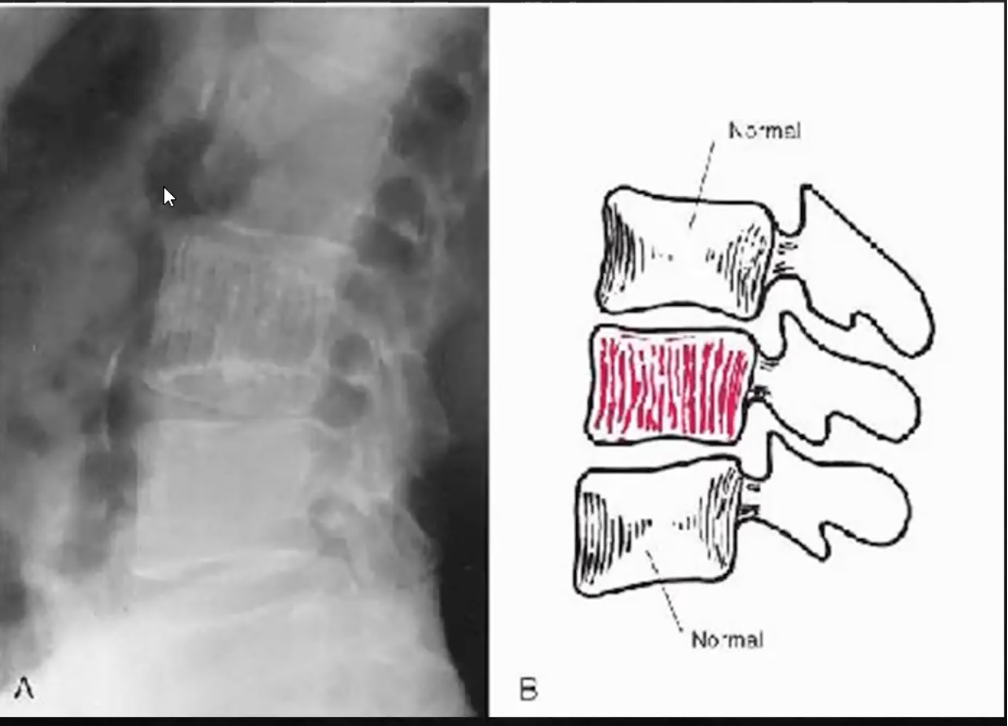

Hémangiome : Bénin mais DOULOUREUX

- 1er plus commune tumeur bénigne de la colonne (squelette axial)

- F > H , > 40 ans

- La majorité des lésions sont dans la colonne

- Colonne : « CORDUROY CLOTH »

- Crâne : « SPOKED-WHEEL APPEARANCE »

- Si apparence de plusieurs hémangiomes, c’est de l’ostéoporose

- DDX : Maladie de paget (mais dans ça, les contours vertébraux sont sclérotique (picture frame vertebrae).